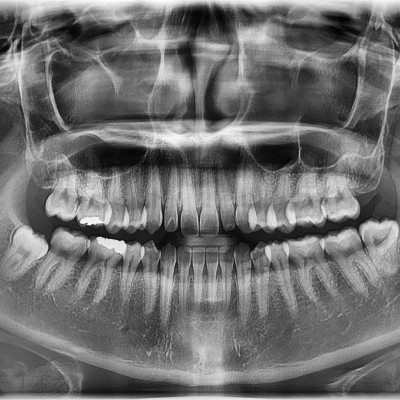

이턱퍼스트치과 사랑니 다양한 사랑니 당일발치가 가능합니다